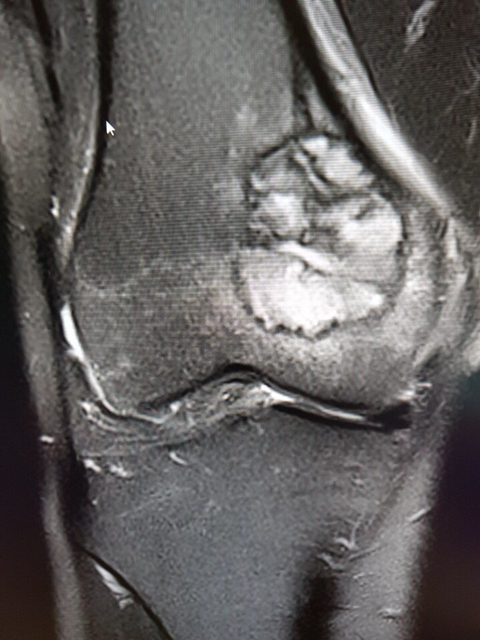

거대세포종 위치와 수술부위는 아래와 같구요...

골시멘트채우고 뼈강도 보강을 위해 철판을 댔다고 합니다.

• 작성자소중한분 작성자 본인 여부 작성자 | 작성시간 18.10.25 오늘 수술후 외래 다녀왔는데 다 나은거라네요~ 수술후 사진보니까 무시무시하네요~ 관절운동 걷기운동 서서히 시작 하라고 합니다. 통증은 일종의 신경통으로 수술로 무릎을 지나는 신경들이 잘려서 여기저기 날카로운 통증이 올수 있디고 합니다. 제가 올렸던 글이 다른 분들께도 참고가 되기를 바랍니다. 댓글 첨부 이미지 이미지 확대